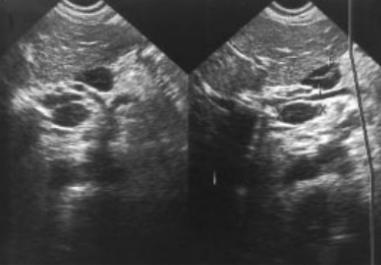

Image echographique de la tuberculose

ileo-caecale est : Image epaissisement hypoechogene de la

paroi du colon et image de lymphadenopathie .